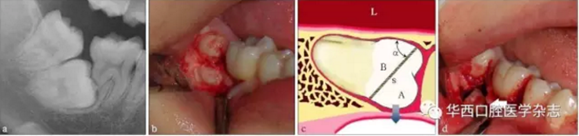

這個(gè)實(shí)際上是最簡(jiǎn)單的運(yùn)動(dòng)力學(xué)原理,物體 O受到周圍物體的抱持緊固而不易脫位,為了便于脫位,可以通過切割,人為地形成一個(gè)斜面,而沿著這個(gè)斜面, A將非常容易脫位,斜面越大,內(nèi)摩擦角α越小,阻力越小。而 A脫位后, B就失去了周圍組織的抱持緊固而易于脫位(圖 1)。具體操作時(shí),需要根據(jù)操作的可及性,靈活設(shè)計(jì)斜面的方向,必要時(shí)可多次分牙。

阻生的 47已造成 46遠(yuǎn)中牙根部分吸收(a),手術(shù)入路較為狹小而受限(b)。為了解除 47脫位阻力,對(duì)牙體進(jìn)行分割(c)。將 47牙切割成A和B,A部分因斜面(s)的存在可沿藍(lán)色箭頭方向順利脫位,并為 B部分的松解創(chuàng)造空間,松解后的 B部分可通過多次分割取出(d)。如此可以盡量減少開窗去骨量,多保留鄰牙頸緣的骨質(zhì)(白色箭頭)。α:內(nèi)摩擦角;L:舌側(cè)。

圖1 斜面原理